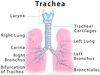

Label the diagram

Label this diagram

Label the diagram

Label this diagram

Label the diagram